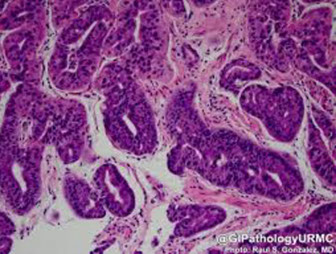

Well-differentiated Neuroendocrine tumors (carcinoid tumors) and other neuroendocrine tumors

Historically known as Carcinoid tumors; they arise from the enterochromaffin-like (ECL) cells throughout the gut

- carcinoid really must have production of serotonin, and cause carcinoid syndrome

- collections of NE cells <0.5 mm known as NeuroEndocrine (NE) cell hyperplasia

- Micro-NE tumors are those 0.5 to 5 mm that are not identified endoscopically

Types:

- classified into several type:

(1) ECL tumors assoc c chronic atrophic gastritis, type A

(2) ECL tumors assoc c ZE syndrome or MEN1 (and hypergastrin secretion from gastrinoma)

(3) sporadic ECL lesions (w/o hypergastrinemia)

(4) Non-ECL tumors

(5) ECL cell tumor c achlorhydria and parietal cell hyperplasia

- autoimmune atrophic gastritis (abs against parietal cells) causes loss of oxyntic glands and mucosal atrophy, causing dec HCl production and hyperproduction of gastrin by antral G cells, causing tumors that can be multifocal

- type 3 (sporadic) lesions are more aggressive, req aggressive surgery

- all have small round proliferating cells

- confirm c NE stains

- graded c mits and Ki67 ([1] = <2 mits/hps or <2% Ki67; [2] = 2-20 mits /hpf or 3-20% Ki67; [3] = HG NE Ca c >20 mits/hpf or Ki67>20%)

- pt gets chemotx if Ki67 >20%

- carcinoid in foregut (stomach and prox duodenum) rarely met and cured c resection

- midgut carcinoids more aggressive

1) Well-differentiated NeuroEndocrine Tumors (WDNETs)

- aka NeuroEndocrine Tumors Grade 1 (NET G1)

MCC, originate from ECL cells

- even well-diff lesions can invade vessels

Tx: If not HG, can be remove endoscopically; possibly somatostatin analogues

Px: Well-differentiated, those that make gastrin have good px and usually don't met, though can met to liver

2) Assoc c ZE syndrome (gastrin-secreting neoplasm, usually in pancreas) and MEN-I; causing hyperplasia of intract parietal cells

IHC: negative gastrin (bc made of ECL cells)

Tx: Regresses c tx of underlying gastrinoma

3) Sporadic, poorly differentiated; may have intact mucosa above tumor if sporadic

Tx: Must treat as gastric carcinoma, with chemotx

Px: most important px factor is location

- worse if >2 cm

Small cell ca can have (+) CD117 and absent KIT mutations

Gastric carcinoid tumors / appendix[?]

Well-diff NE tumor

Carcinoid with nesting, rosetting, and pseudoalveolar forms